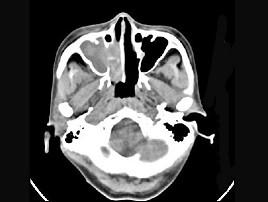

问题 女性,53岁,右侧鼻腔流血近一年,近来头痛,行CT检查如图所示,请选择正确的答案 ( )

选项 A、鼻腔炎性假瘤 B、鼻腔内血管瘤 C、鼻腔内息肉 D、副鼻窦炎 E、鼻腔癌

答案 E